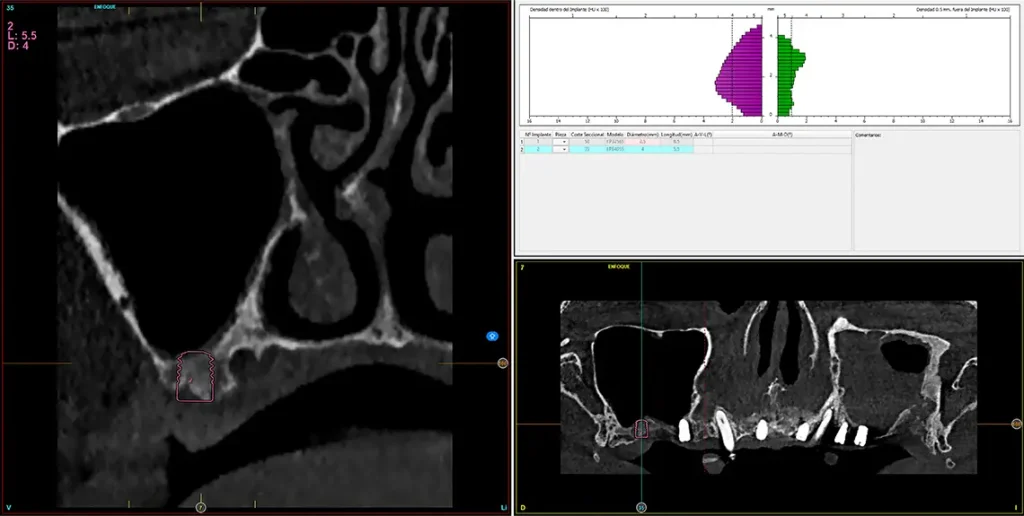

Para realizar una planificación precisa del caso y determinar el volumen óseo residual antes de la cirugía implantológica, se realiza un estudio mediante tomografía de haz cónico (cone-beam) y se visualiza mediante un software específico (BTI-Scan IV). Esta exploración permite medir con exactitud la altura y anchura de la cresta ósea, así como evaluar la densidad de las zonas en las que se prevé colocar los implantes, facilitando así una planificación quirúrgica fiable y ajustada a las necesidades anatómicas del paciente44–47. En las imágenes del cone-beam de control, observamos en el segundo cuadrante una atrofia vertical extrema, con zonas de menos de 4 mm de altura, donde se planifican implantes de 4,5 mm de longitud que serán colocados mediante el procedimiento de elevación transcrestal con fresa de corte frontal y con hueso autólogo obtenido del fresado embebido en PRGF-Endoret como material de injerto. Esta técnica, descrita por nuestro grupo de estudio, nos permite realizar un abordaje seguro del seno maxilar con una escasa invasividad (figs. 8-10)9,25,29,36.

Figs. 9-10. Medida de la zona con mayor atrofia del segundo cuadrante menor a 4 mm de altura y planificación del implante de 4,5 mm de longitud que será colocado mediante el procedimiento de elevación transcrestal anteriormente descrito.